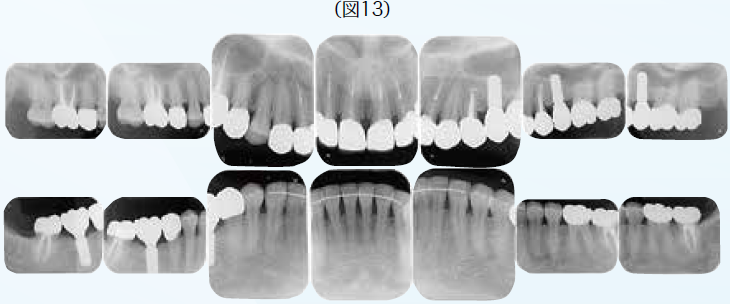

ブリッジの支台歯になっていたため応急処置として補綴装置は除去せず、そのままで抜髄処置を行なった。他に症状として右下7番の知覚過敏も呈していた。顎関節症状としても関節部に違和感があり、片頭痛も持ち併せているということで、病的咬合の疑いがあり、全顎的な診査・診断を行うこととした。10年前に母国韓国にて全顎的に審美修復がなされていたが、咬合面形態はかなり咬耗しバーティカル・ストップが喪失していた。アンテリアの状態も犬歯関係はⅢ級気味でアンテリア・カップリングが不良な状態で顎運動時に臼歯に負担がかかっていることが予測できた。前歯が無髄歯になった原因は審美修復をする際に便宜的に抜髄されたからである。臼歯部が抜髄に至った歯髄炎や既に無髄歯になっていて根尖部に病変が存在して再治療が必要な歯の病態に陥った原因は荷重負担によるものと推測できた。臼歯部における適正なバーティカル・ストップと咬頭干渉を起こさないために、アンテリア・カップリングの確保のために全顎矯正を含めた全顎的な咬合再構成を行うこととし、欠損部に関しては支台歯の負担軽減のためインプラントを用いた修復処置を計画した。

初期治療において炎症のコントロールを徹底するため、歯周治療と並行して、不良補綴装置を除去してプロビジョナル・レストレーションを装着し、感染根管歯は全て再治療を行なった。初期治療終了後、矯正治療を行なった。矯正学的診断が骨格性Ⅰ級で上下顎前突傾向があり、下顎前歯部の叢生によって犬歯関係はⅢ級関係を示していた。矯正治療を行うことで歯の位置関係が改善したことを確認したのち、確定外科をインプラント治療と合わせて行い、再評価の後に補綴処置を行なった。デジタル機器を用いることで機能的にも審美的にもまた患者の要求にも対応しやすくなった。補綴処置終了後再評価を行いメンテナンスに移行した。治療期間4年で術後4年近く経過したが、無髄歯の根尖周囲組織も有髄歯の歯髄の状態も良好に経過している。欠損部にインプラントを用いたことによってブリッジの支台歯になっていた無髄歯の予知性も向上したと考える。(図2〜図14)